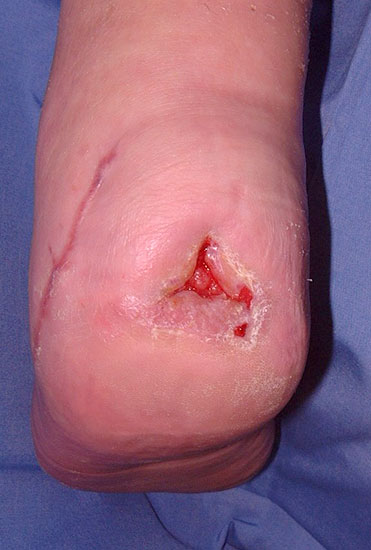

Nekrose an der Großzehe (Abb. 2)

Eitrig-infiziertes Ulkus an der Spitze der 2. Zehe als Indikation zur Endgliedamputation.

Chronisches Ulkus mit Infektion (Abb. 13).